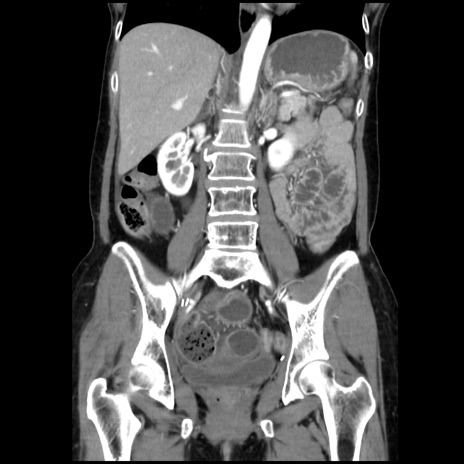

症例32(冠状断像)

【症例】40歳代 女性

【主訴】上腹部痛、嘔気・嘔吐

【現病歴】約9時間前頃から急に上腹部痛、嘔気、嘔吐が出現。改善しないため救急要請。

【既往歴】子宮頚癌(広汎子宮全摘術、放射線療法)、腸閉塞

【身体所見】腹部:平坦、軟、腸雑音亢進、上腹部を中心に腹部全体に圧痛あり。

【データ】WBC 8400、CRP 0.03